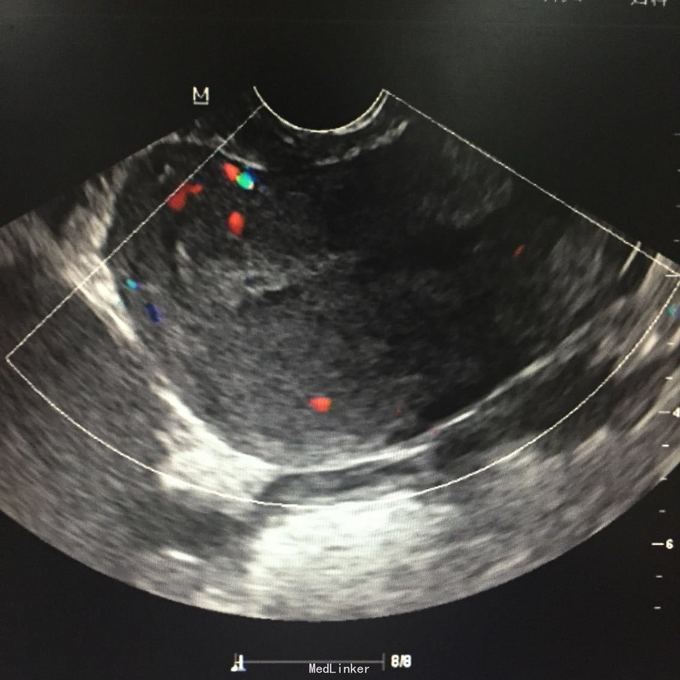

查体:右侧附件区可及一10*5cm包块,囊性,无压痛、反跳痛,左侧附件区可扪及5*5cm包块,囊性,轻压痛,无反跳痛。辅助检查:彩超:筛查附件区囊性包块,考虑内膜异位囊肿可能性大,左侧一个,大小58*49mm,右侧多个融合,范围91*48mm。